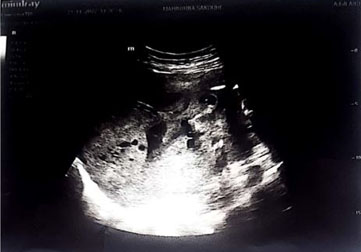

The patient was anxious, tachypneic with an SpO2 of 37%, febrile, and physical exam revealed bilateral rhonchi. She was placed on supplemental oxygen at 15 liters with minimal improvement of her oxygen saturation. Computed tomography (CT) scan of the chest showed diffuse ground glass opacities (Figure 1) and due to her worsening respiratory status, she was admitted to the intensive care unit for management and was intubated upon arrival to her room. She was started on high dose dexamethasone, remdesivir, and required norepinephrine for hemodynamic support. Continuous fetal monitoring and an increased steroid dose for lung maturity in case of early delivery were recommended by the Obstetrics team. With the patient’s PaO2 being of concern, she received many arterial blood gas analyses (ABGs) during her care, with a total of 27 ABGs analyzed (Figure 2). These results were consistent with COVID sepsis and acute hypoxic respiratory failure. The patient’s positive end-expiratory pressure (PEEP) (Figure 3) and oxygen requirements continued to rise with little improvement in clinical status, so the decision was made to start her on a paralytic infusion as well as place her in a semi-prone position (Figure 4) to allow for continuous fetal monitoring and uterine displacement. Initially, oxygenation improved with the semi-prone position. However, on hospital day 7, significant subcutaneous emphysema was noted as well as the continuous need for a PEEP value of 20 cmH2O and 100% FiO2 to maintain appropriate oxygenation.

Figure 1: Computed tomography (CT) showing diffuse geographic ground glass pulmonary opacities.